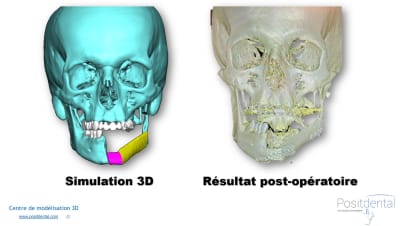

Protocole de modélisation 3D pour greffe de Fibula avec guide de coupe de péroné et d’ostéotomie mandibulaire.

Vous souhaitez découvrir les dispositifs de coupes sur mesure réalisés en acier chirurgical: [email protected]

#guide de #coupe de #péroné #Fibula #chirurgie #3d #simulation